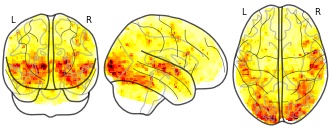

"name": "Multi_VBMsmaller_fMRIdecreased",

"description": "Multi-modal analysis in BPD. Brain regions exhibiting smaller gray matter and decreased activation during emotion processing in BPD compared to healthy controls. Note: Results were thresholded at p<.0025. Note2: Results were updated (see Erratum for this publication).",